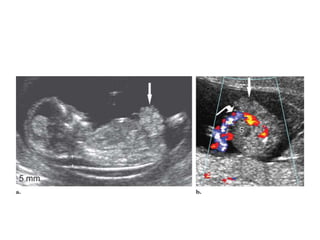

Gebelik haftası

arttıkça anomali

yakalama oranı

artar